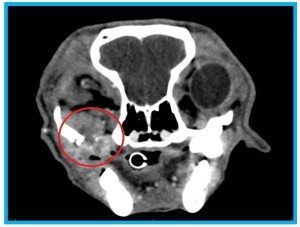

This CT image demonstrates the invasive growth pattern that many melanomas exhibit. This dog had a 3 cm pigmented gingival mass present within the mouth, along with pain on opening the jaw and some facial swelling. The CT scan showed significant invasion of the mass through the maxilla and the zygomatic arch, with extensive soft tissue invasion in the retrobulbar space (outlined).